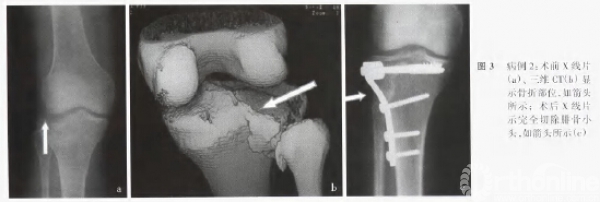

5例患者诉阴雨天膝关节酸痛、不适,但不影响活动,无踝关节疼痛,无小腿及足部感觉障碍。全部患者步态正常、无内外翻畸形。膝关节稳定性检查中,3例出现关节外侧直向不稳,其中2例为完全切除腓骨小头,1例为部分切除腓骨小头;无膝关节旋转不稳。全部患者患足外翻、外旋肌力与健侧对比无明显异常。1例出现拉力螺钉松动,向外侧退出约3mm,对骨折愈合及关节功能无影响,无内固定断裂。术后x线片检查,2例患者出现胫骨平台高度丢失分别为2mm和4mm,均系因过早负重所致,但无膝关节不稳和疼痛等症状。其中53例患者于术后1.5~2.0年取出内固定,术中发现上胫腓关节间有大量的坚韧瘢痕组织形成(图3)。